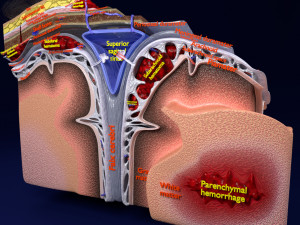

A blend model of brain along with its covering layers (meninges), skull bone and scalp labelled in detail and anatomically precise. The parts depicted are white, gray, pia, arachnoid, dura, bone, skin, fat, aponeurosis, periosteum, falx cerebri and more.

The material is high resolution image textures and normal maps based on non overlapping UVs. The texture and normal maps are packed with the blend file itself.